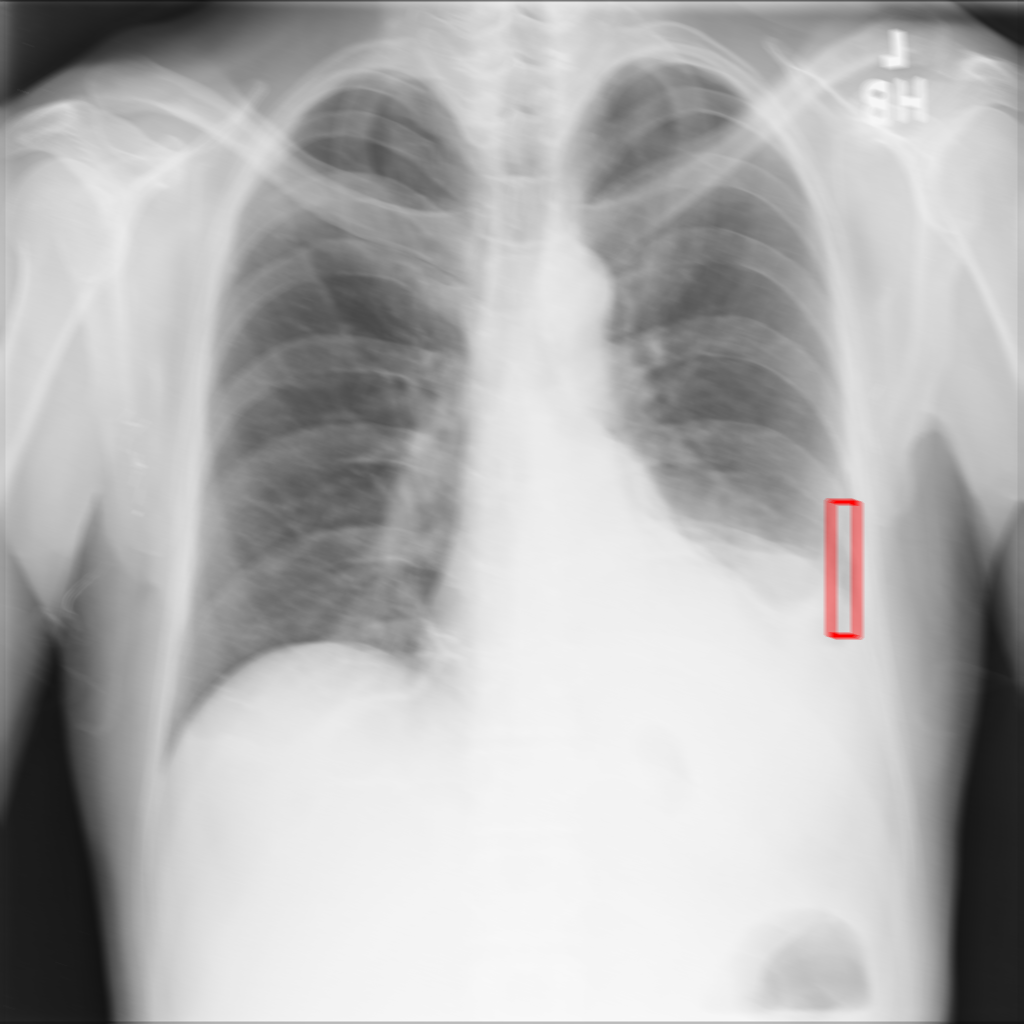

X-ray Motion Blur

X-ray GMAIMMbench Disease Diagnosis

X-ray Motion Blur - L0 (Original)

L0

L0 (Original)

X-ray Motion Blur - L1 (Moderate)

L1

L1 (Moderate)

X-ray Motion Blur - L2 (Severe)

L2

L2 (Severe)

Question

Considering the box-marked region in the X-ray image, what is the most likely diagnosis?

A cardiomegaly B pneumothorax C pulmonary nodule D pleural thickening

Ground Truth: B. pneumothorax